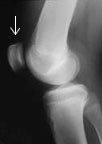

One needs generally to take another picture from the side to see the other dimension. This is called a 'lateral' view. Now you can see that femur and patella are in different planes.

The Lateral (side) view can be technically difficult. In order to get an x-ray that is in the correct plane, the x-ray technician may have to rotate the leg this way or that way until he or she gets it right. By always seeing a standard view doctors can develop confidence in interpreting the films.